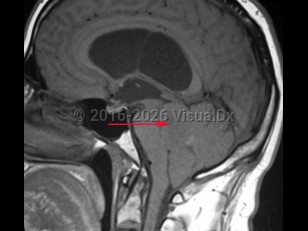

Imaging Studies image of Ependymoma - imageId=8342748. Click to open in gallery.  caption: '<span>T1 weighted sagittal MRI demonstrating ependymoma of the fourth ventricle.</span>'

T1 weighted sagittal MRI demonstrating ependymoma of the fourth ventricle.